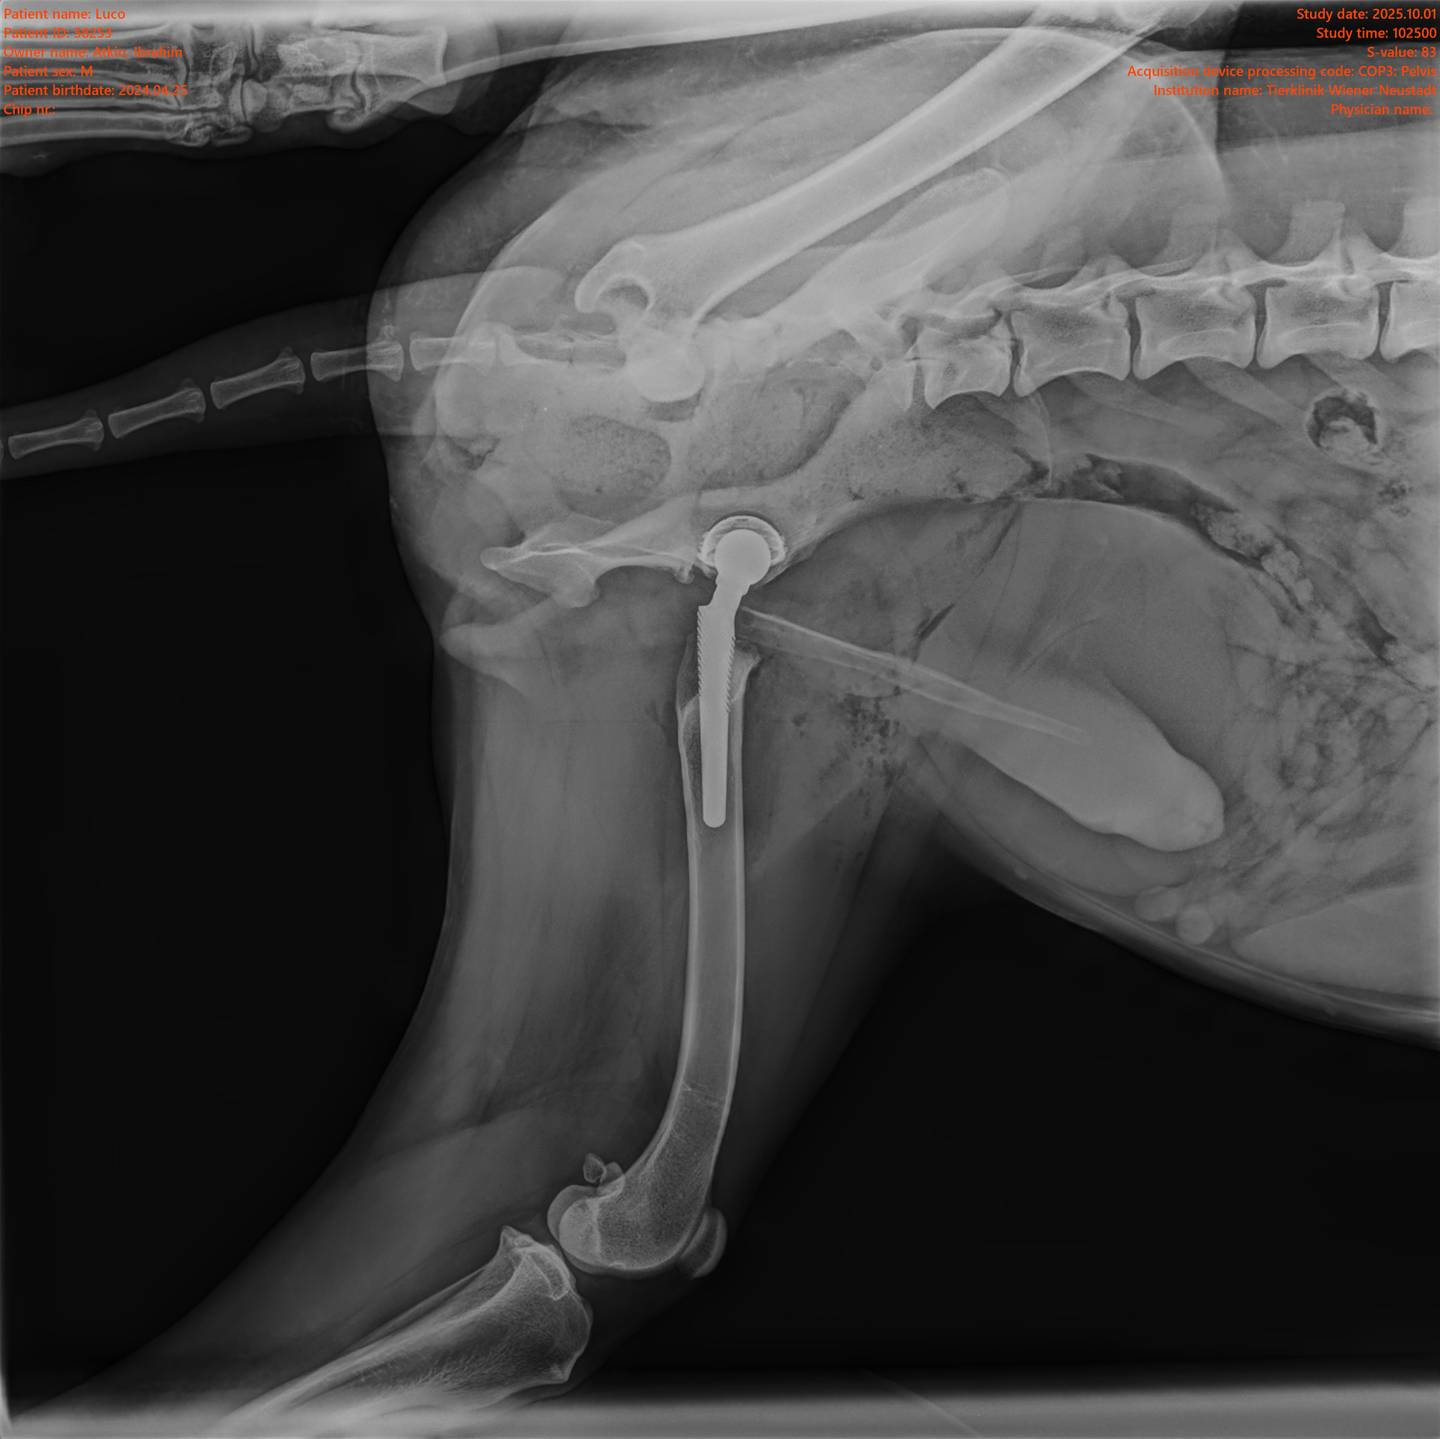

Unser Spezialisten-Team sowie modernste technische Geräte ermöglichen das Angebot eines breiten Spektrums professioneller und komplexer Leistungen. Wir bringen unser medizinisches Wissen in allen Fachbereichen laufend auf den neuesten Stand. Eine strategische Vorgehensweise zur Abklärung der Erkrankung mit dem Ziel, klare Diagnosen zu stellen, hat für uns oberste Priorität. Unsere Tierärzte sind spezialisiert auf Kleintiere und Heimtiere. Zu diesen gehören Hund, Katze, Kaninchen, Meerschweinchen, Frettchen, Hamster, Maus, Ratte und Chinchilla. Wir möchten ausdrücklich darauf hinweisen, dass wir für die Behandlung anderer Tierarten nicht entsprechend ausgestattet sind und daher nicht annehmen. Dazu gehören unter anderem auch Vögel und Exoten.

Tierklinik Wiener Neustadt